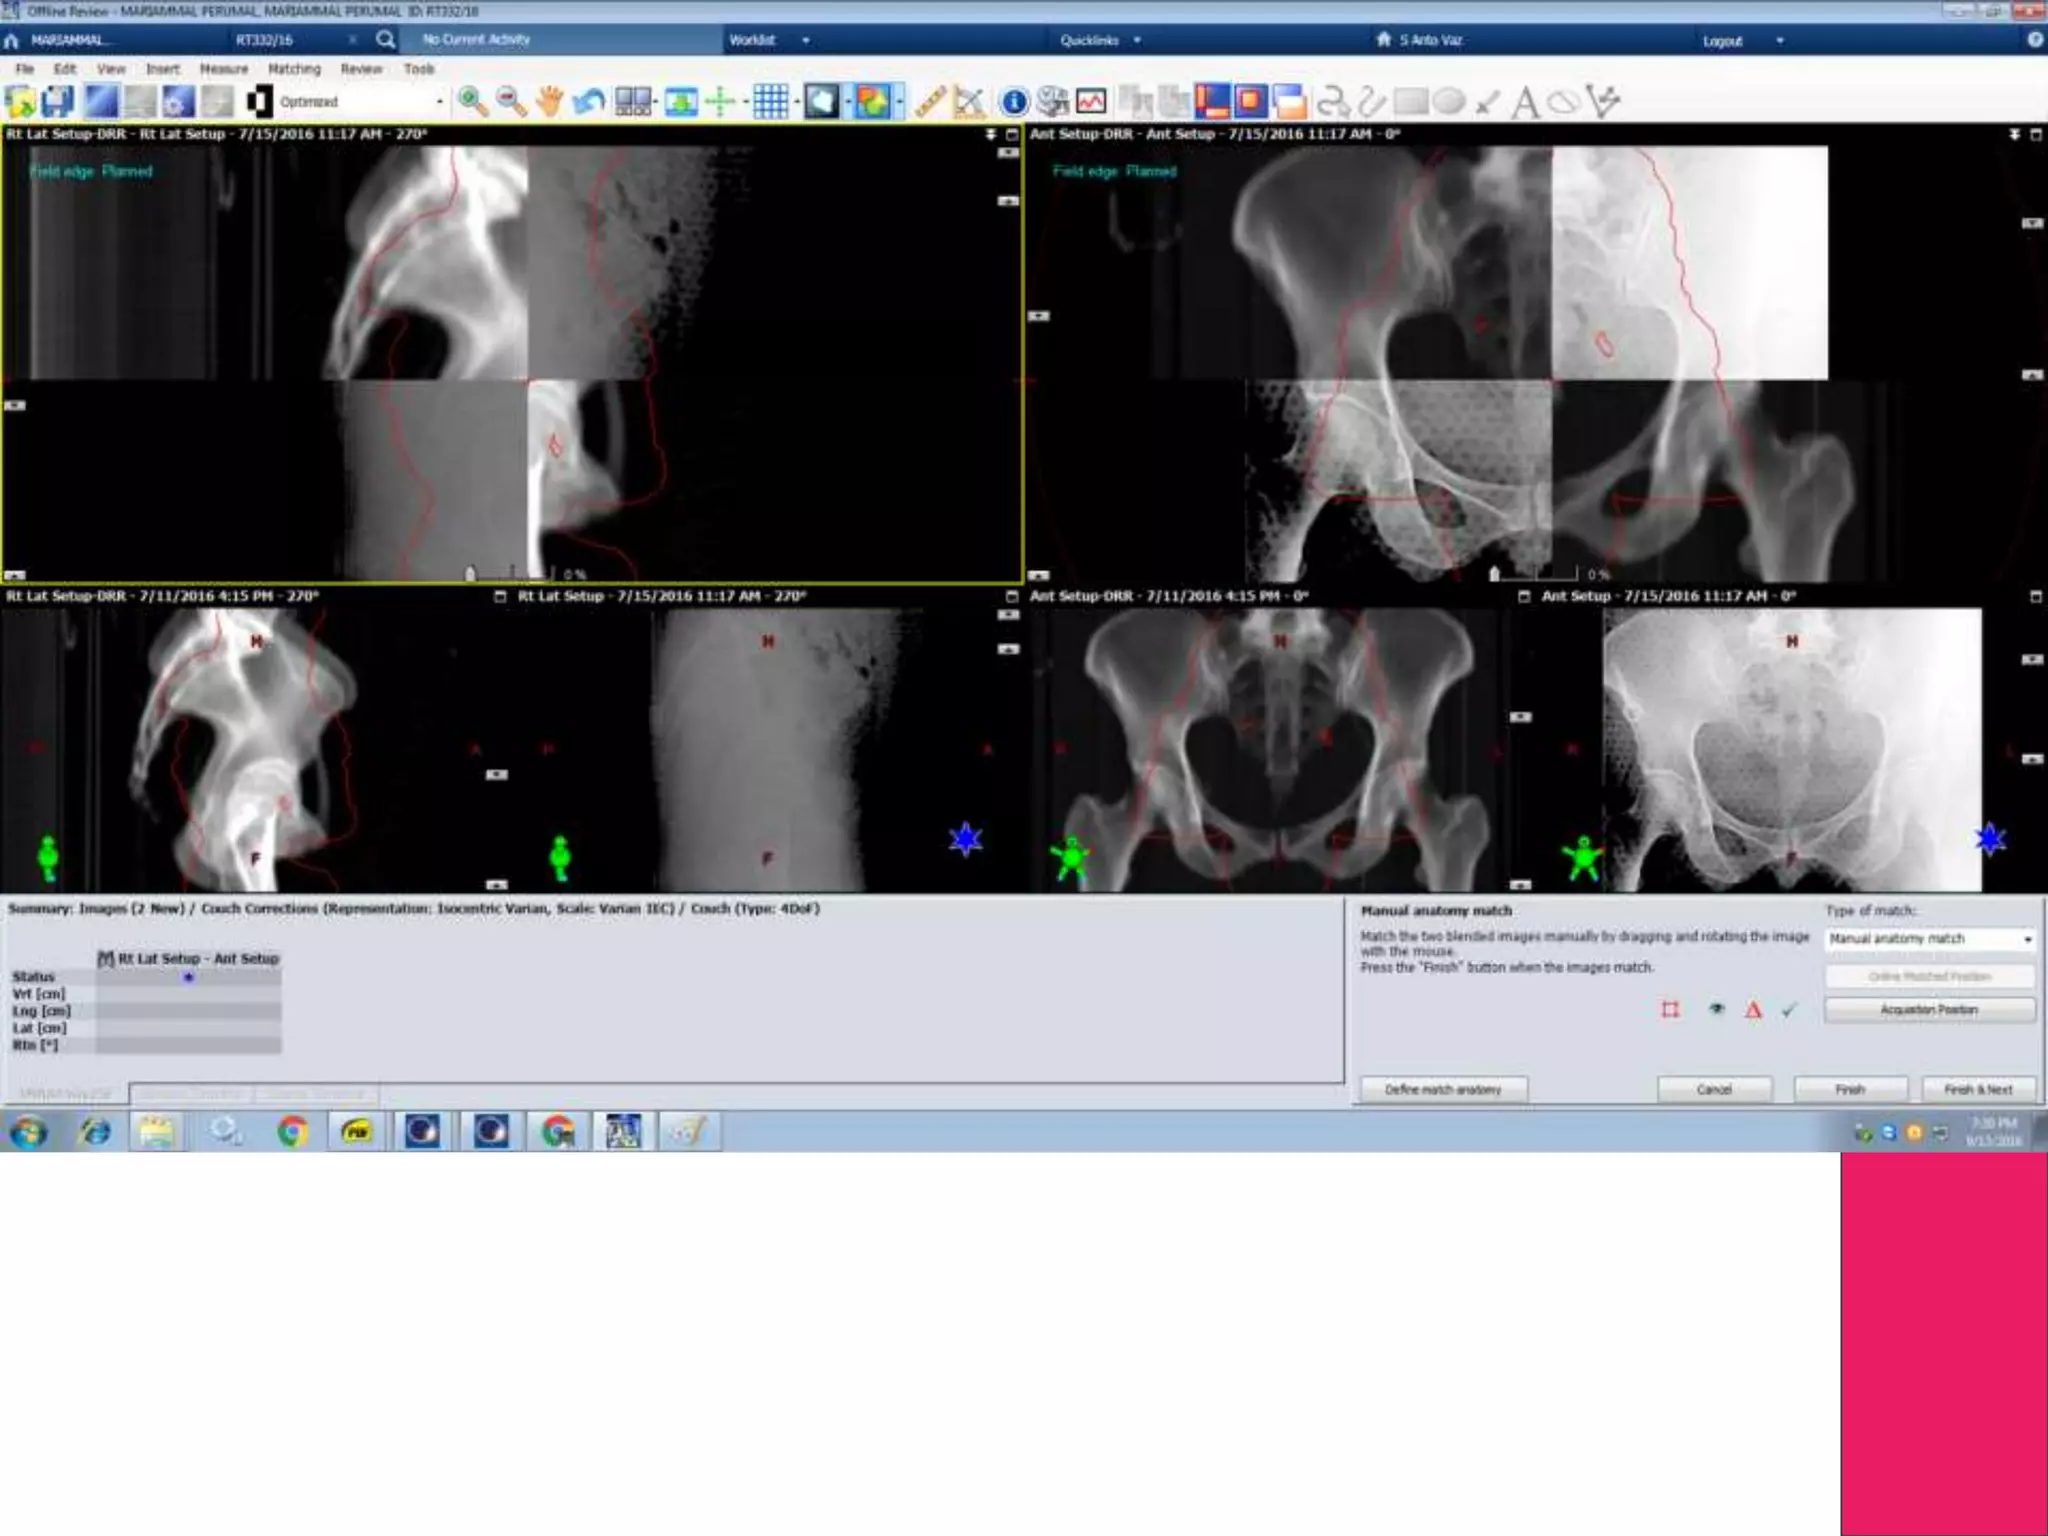

IGRT

Image Guided Radiotherapy, will use either 2D(Xray) or 3D

imaging (Cone Beam CT)

Linear Accelerators will have capability of doing a Xray and CT

Recent Development is Linac with MRI- !

Ensure the Efficiency of Treatment with the help of Imaging

Change in Anatomy can be found during treatment and corrected

IGRT Image Guided Radiotherapy,will use either 2D(Xray) or 3D imaging (Cone Beam CT) Linear Accelerators will have capability of doing a Xray and CT Recent Development is Linac with MRI- ! Ensure the Efficiency of Treatment with the help of Imaging Change in Anatomy can be found during treatment and corrected